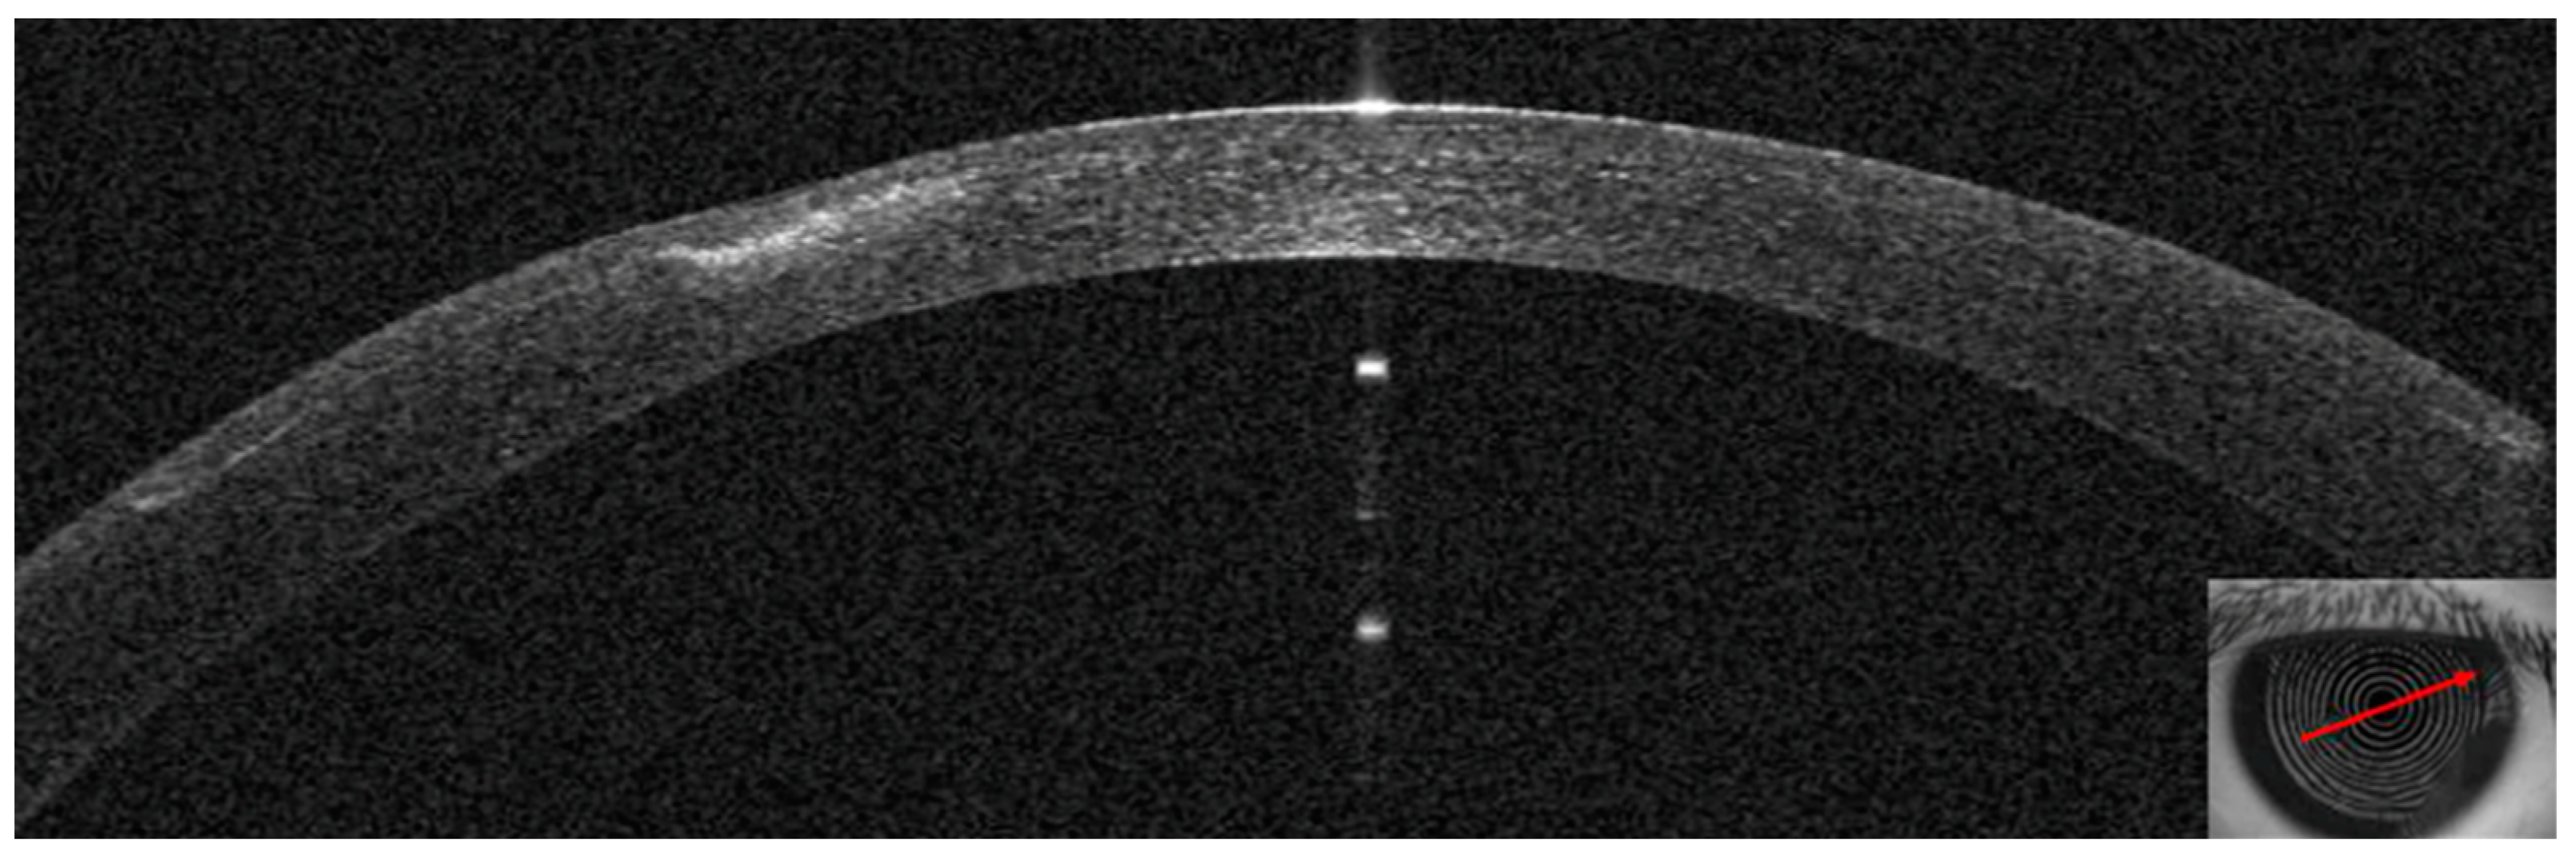

3.1. Patient #1

3.2. Patient #2

3.3. Patient #3

3.4. Patient #4